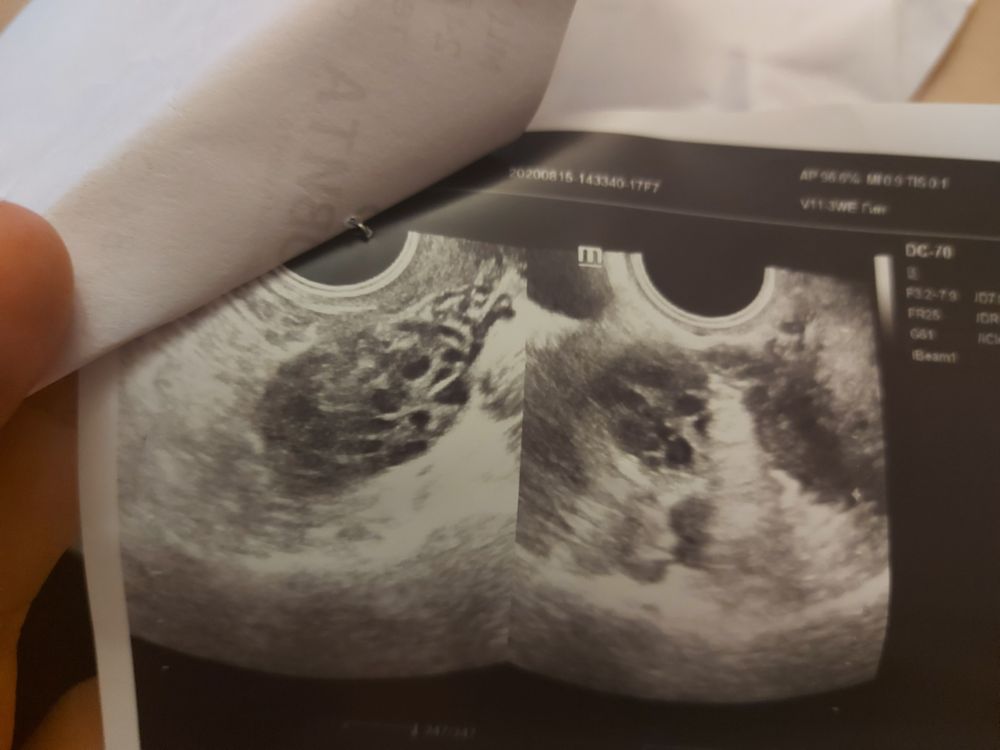

Почти год не получается забеременеть. Месячных нет по 2-3 месяца.Была на узи и сдавала на гормоны,может кто понимает в этом?

Мари, не поверите,у 3 х врачей была...и не один толком ничего не сказал...по узи даже подозрение поставили на полткистоз и то под вопросом.и говорили, чтобы пила таблетки от воспаления..и толку никакого. Щитовидку сдавала, все хорошо. На гормоны тоже ФСГ,Свободный тестостерон,прогестерлн, пролактин.

Что врач имел в виду «строение не соответствует»?Мне кажется что 3 мм на 7 дц тонковат немного эндометрий,хотя может нарастет ещё,разгонится. По сколько дней длятся месячные?